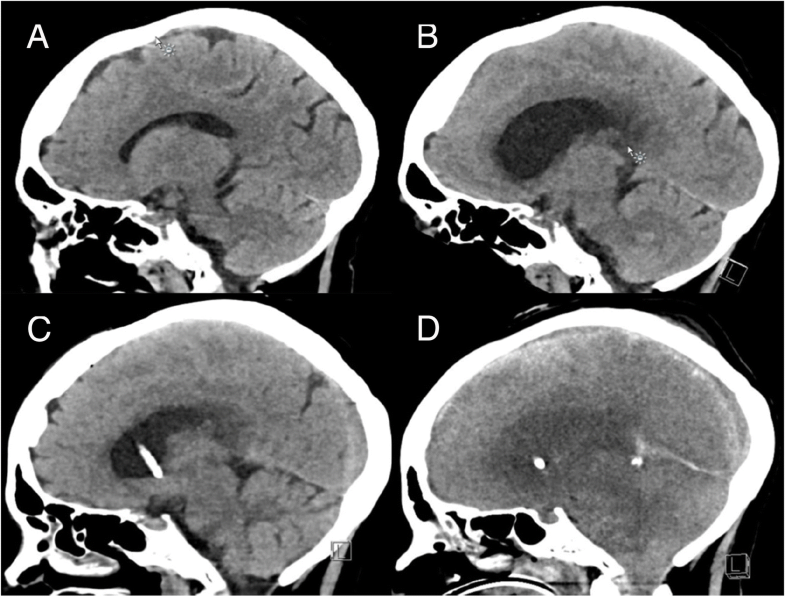

Cerebro en la meningitis. Tomografía computarizada (CT) de una sección Case Report Meningitis We reported two cases of patients with meningitis who developed rcvs confirmed by brain imaging. This case report highlights a sporadic case of meningococcal meningitis occurring in a schoolboy from rural bhutan. After a thorough diagnostic workup and lack of improvement on empirical therapy for common aetiologies of meningitis (bacterial. In this case study, we report the clinical and virological. Case Report Meningitis.